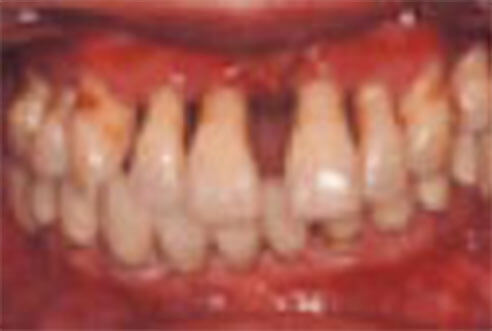

歯肉の色:赤紫色

歯肉の形態:歯と接している歯肉がさらにぶよぶよと腫れ、退縮する。ブラッシングで血や膿がでる。歯と歯の間が広がり、食べ物もよく詰まる。歯肉が退縮して、歯が長く見える、炎症はさらに進み、歯周ポケットはどんどん深くなり、深部のプラーク内の細菌は強い毒を出し、骨(歯槽骨)を溶かして破壊します。